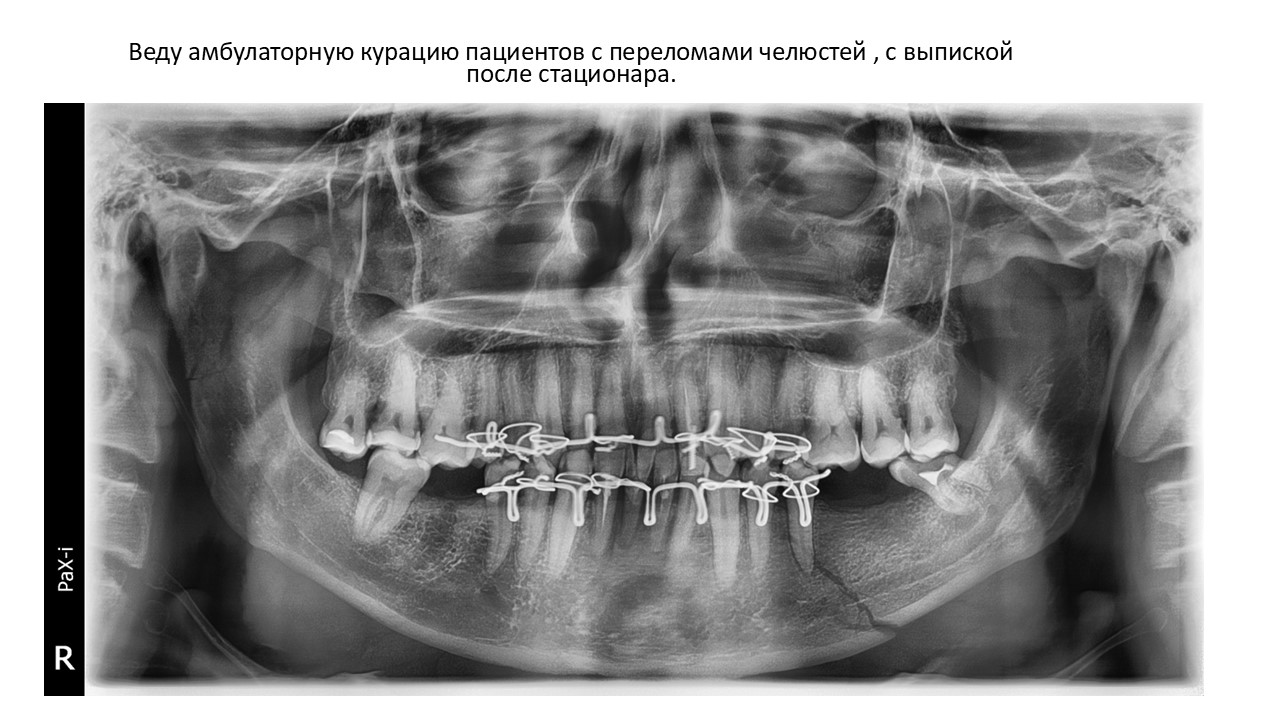

Презентация достижений (загрузите до 10 слайдов отдельными изображениями в формате .jpg)